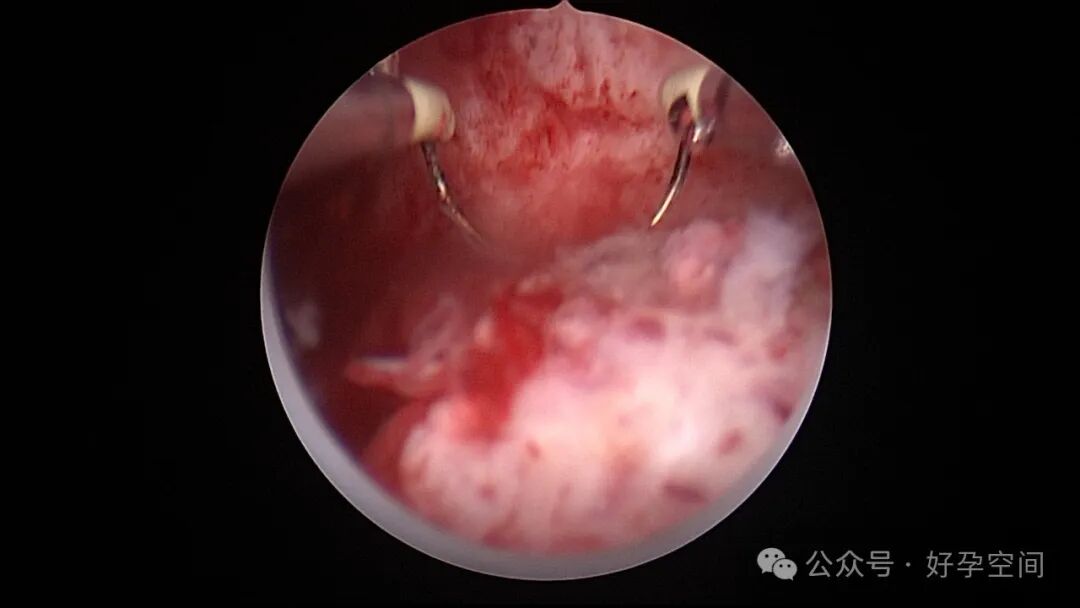

病例3:26岁,孕产史不详,本次停经60+天,稽留流产,宫腔镜辅助下清宫,见剖宫产瘢痕憩室,左侧宫角2.0cm*1.5cm组织凸起,难以清除,宫腔镜电切送病检,病检结果为蜕膜组织及平滑肌组织。

病例4:34岁,G3P1,顺产1次,本次停经40+天,计划外妊娠,宫腔镜辅助下清宫,宫腔前壁2.cm*1.0cm组织难以清除,家属拒绝切除送病检,术后2周复查B超,宫腔查见1.1cm*1.0cm占位,无血流信号,门诊随访。